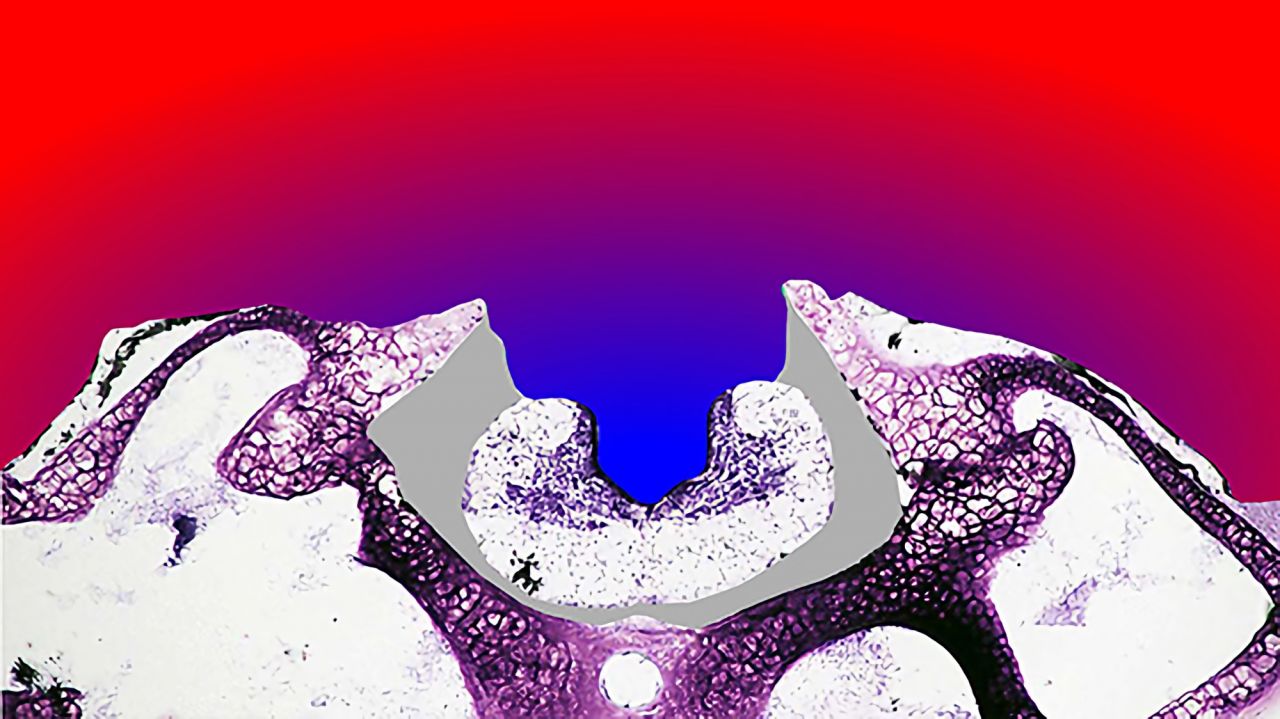

Aufbau des Gehirns MED4LIFE.

Hessischer Bildungsserver